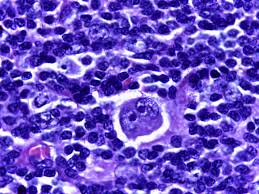

Hodgkin lymphoma is an extremely rare type of lymphoma making up about 10 percent of all cases of lymphoma all over the world. The most distinctive feature for HL is its presence Reed-Sternberg lymphoma cells which are huge abnormal lymphocytes, visible under microscope. These cells play a crucial part in diagnosing the condition.

There is a presence of Reed-Sternberg cell within HL and the consistent pattern of spreading are the most significant distinguishing characteristics. NHL is a complex disease, with a variety of subtypes, is more difficult to recognize and manage effectively.